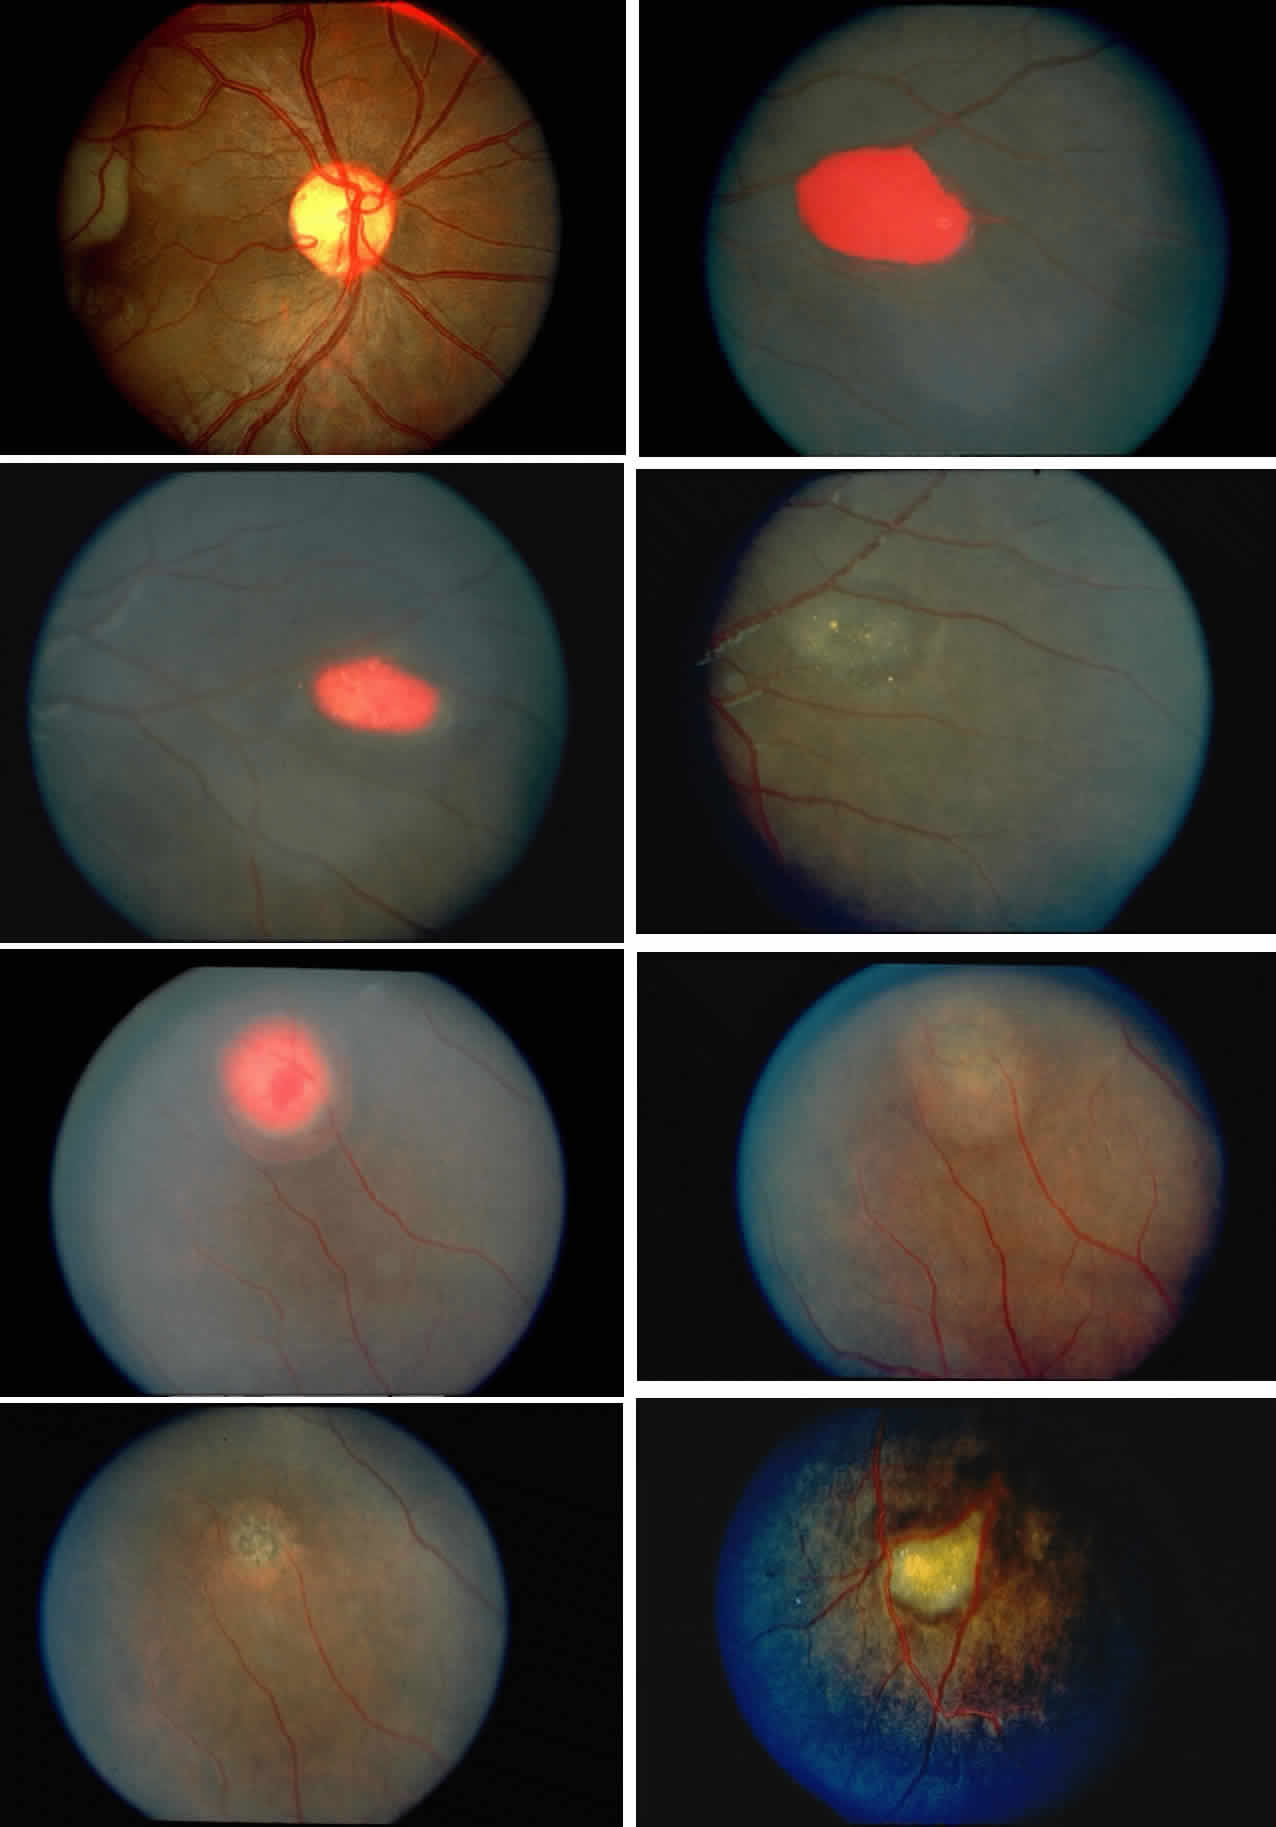

Disc Sign

Transient dark red spots (similar to conjunctival commas), representing plugs of sickled erythrocytes within superficial capillaries, may be seen on the surface of the optic disc (Fig. 3 and Color Plate 1A). These disc changes are not associated with any functional or anatomic abnormalities. They are found in 11% of all patients with sickle cell disease, but appear to be more common in patients with homozygous sickle cell anemia, occurring in 29% of these patients.67 The disc sign correlates with the presence of conjunctival commas and ISCs.

Retinal Hemorrhages, Iridescent Spots, and Black Sunbursts

Retinal hemorrhages (“salmon patches”), found most commonly in the equatorial periphery, can be observed after an abrupt occlusion and rupture of an intermediate-sized retinal arteriole (Fig. 16).113 Because the hemorrhages typically appear adjacent or distal to an intraluminal obstruction, it is likely that ischemic necrosis causes a weakening of the vessel wall and that reperfusion of the vessel causes a rupture of the damaged vessel wall, resulting in a hemorrhage (Fig. 17).100 Acutely, these hemorrhages are bright red, but after several days, the partially degenerated blood acquires a characteristic orange-red color (hence the name salmon patch). In most cases, these hemorrhages are asymptomatic. The majority of these hemorrhages remain confined to the sensory retina; however, blood may leak through the internal limiting membrane into the vitreous or dissect deeper into the subretinal space (Fig. 18).114 Resolution occurs over days to weeks and may result in a focal area of atrophic split retina (a “schisis” cavity), a pigmented retinal scar, or a grayish-white vitreous deposit, depending on the location of the hemorrhage (Color Plate 1B through G).115 The blood is slowly cleared by macrophages.

Intraretinal blood breakdown products, either extracellular or within macrophages, may appear as refractile copper-colored granules (“iridescent spots”") (Color Plate 1H). Macular iridescent schisis lesions have not been described clinically, but they have been observed on histologic examination.114

|

Black pigmented spiculate or stellate chorioretinal lesions (“black sunbursts”) are typically found around or anterior to the equator and adjacent to an arteriole.70 Occasionally, a pigmented lesion may be seen trailing from an arteriole or as a cuff of pigment overlying the vessel (Color Plate 2A).83 Additionally, the overlying arteriole may be occluded. Refractile deposits are often seen interspersed with the pigment. Black sunbursts are believed to be due to deep retinal blood stimulating pigment epithelial migration, hyperplasia, and hypertrophy.116,117 Histopathologic findings support this hypothesis,114 and the development of black sunbursts has been documented in an area of previous intraretinal and subretinal hemorrhage (see Color Plate 1E, F, and G).114,115 An alternative explanation for black sunbursts is the occurrence of choroidal ischemia and aborted choroidal neovascularization.22,118 A spontaneous chorioretinal neovascular membrane was shown to occur within a black sunburst in a 14-year-old girl with homozygous sickle cell anemia.119